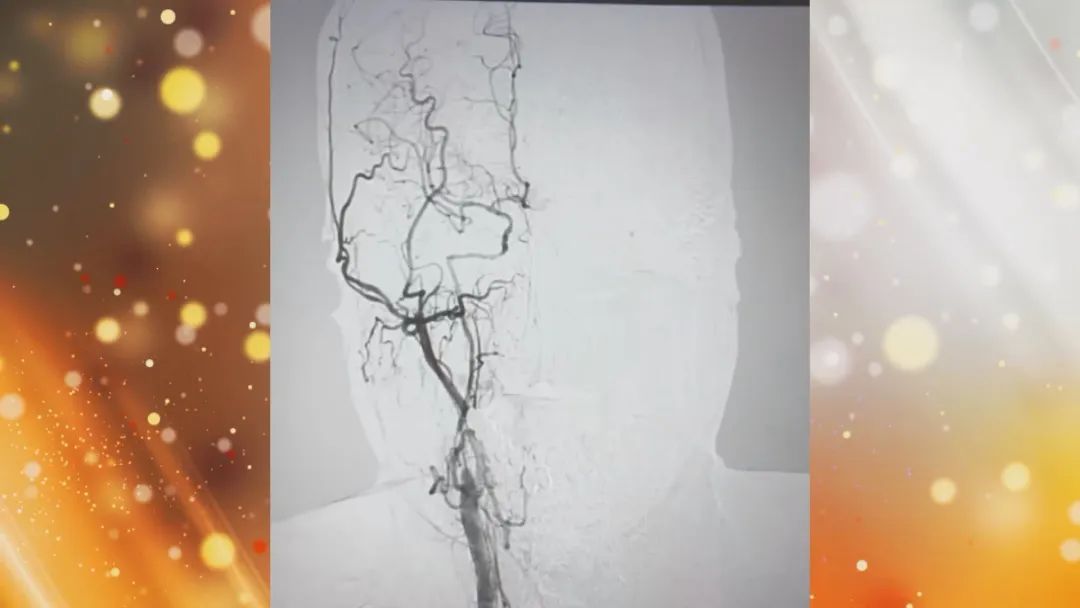

脑部不同的颜色区域分别代表脑血管的供血状态,很多时候这种慢性闭塞引发的缺血我们根本就感觉不到,这种慢性缺血的出现不会直接发生紧急状态,甚至缓慢的缺血还会促使侧支循环建立,进一步出现代偿去补救脑部的缺血,但是“慢刀子”更伤人,这种自救的同时也会掩盖脑血管闭塞的问题,让疾病一步步走到严重阶段,所以这种慢脑梗比急性脑梗更危险!

作为外科手术中难吭的硬骨头,专家带来直观的脑血管打通手术,亲眼目睹如何疏通大脑“生命线”,那究竟什么样的人群需要去主动开通?